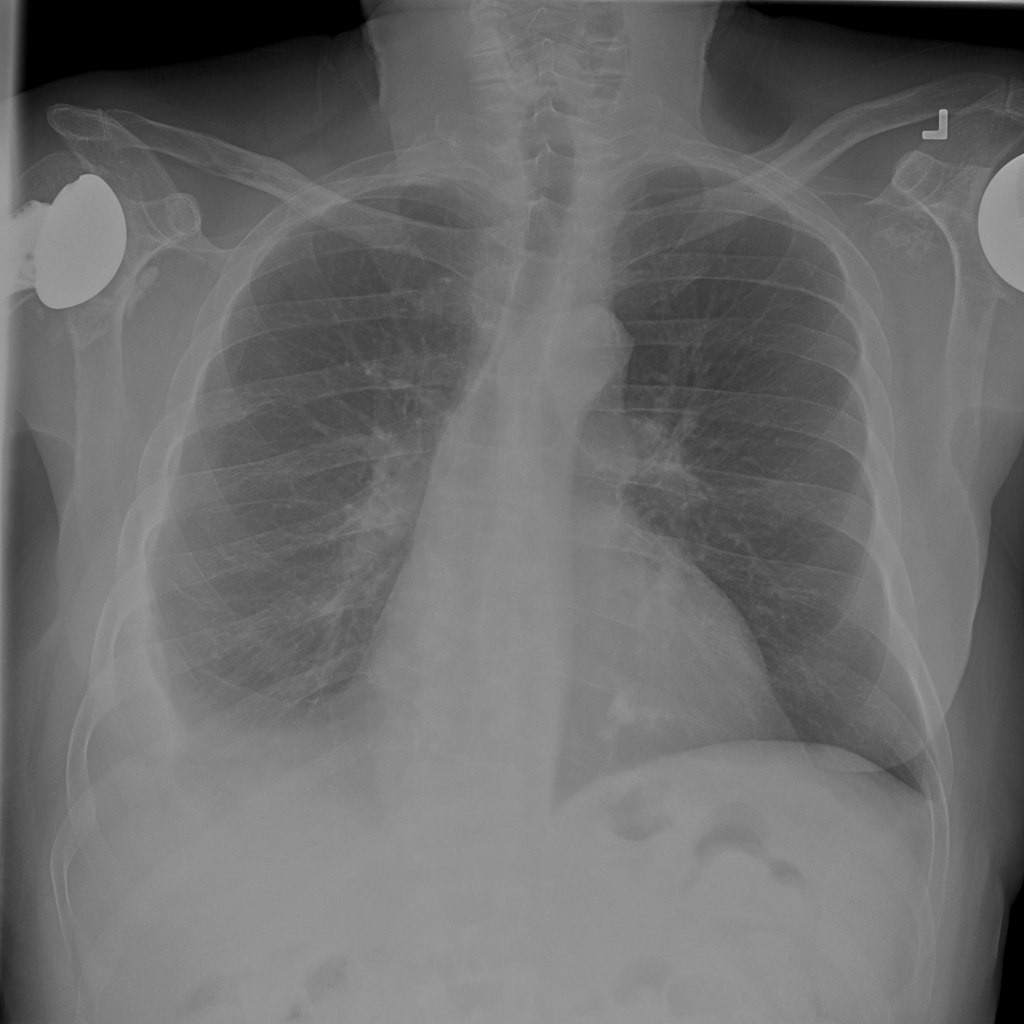

PAT-40F9 · IMG-004Effusion

PAT-40F9 · IMG-004

PA